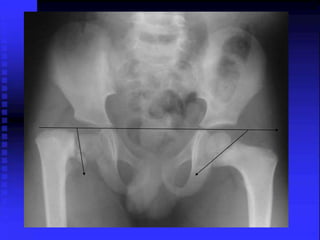

Developmental Coxa Vara

Hilgenreiner’s Epiphyseal angle

200-250

Surgery is indicated in

= H.E. angle > 45 degrees

= NS angle < 90-100 degrees

= Trendelenburg gait

= Limping